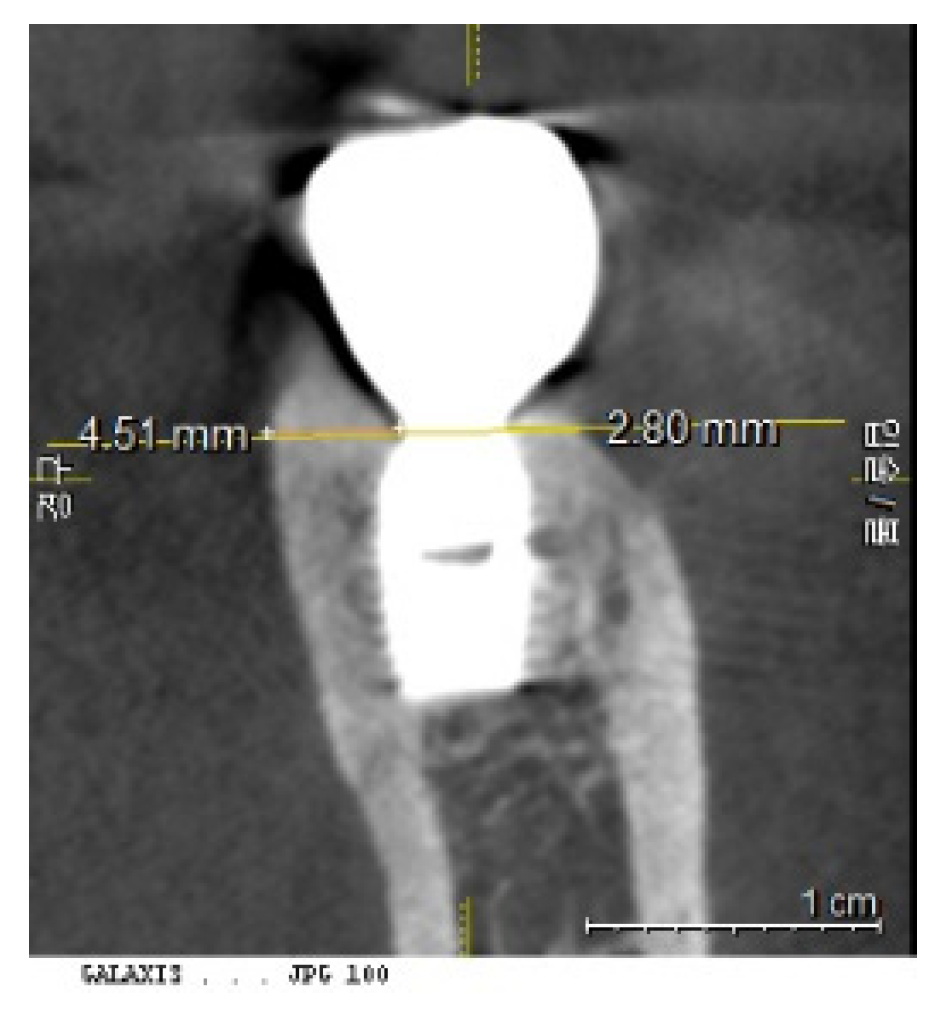

Figure 3 and Figure 4: Impact of Implant Placement Depth on Clinical Crown Shape

These figures demonstrate the effect of the depth of implant placement on the shape of the clinical crown. Figure 3 shows an equicrestal placement of a second molar implant, where insufficient vertical space necessitates a smaller diameter or an abrupt emergent profile for the clinical crown. In contrast, Figure 4 illustrates a subcrestal placement for a first molar implant, which provides sufficient vertical space allowing for the creation of a more natural-looking clinical crown with a gradual emerging profile.

Figure 3. Case Study of Epi-Crestal Placement of a Second Molar Implant. This figure illustrates a case where a second molar implant was placed epi-crestally, resulting in a smaller clinical crown size and an unnatural appearance due to an improper emergent profile compared to the adjacent natural molar. This outcome is attributed to the shallow depth of placement, which causes the transition part to be exposed supramucosally.

Figure 4. Comparative Case of Equicrestal vs. Subcrestal Implant Placement. This figure demonstrates the differences between equicrestal and subcrestal implant placements. For the implant in the position of the second molar, equicrestal placement results in a molar diameter reaching a short vertical distance, leading to an abrupt emergent profile with the transition part located supramucosally. In contrast, for the implant in the position of the first molar, subcrestal placement yields a more natural appearance, as it allows for a gradual emergence with the vertical distance matching the horizontal distance needed for diameter increase, and the transition part located submucosally.